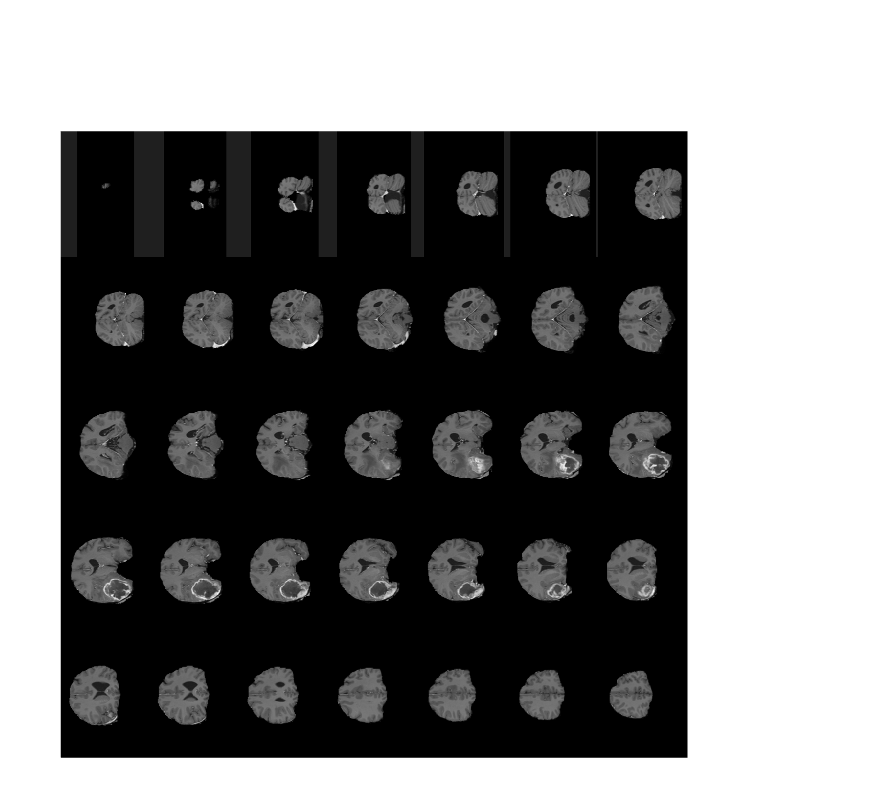

Display horizontal slices of the data by using the montage function.

montage(V,'Indices',12:118,'Size',[8 12],'DisplayRange',[]);

Display the extracted image slices by using the montage function.

figure montage(Bslices,'Size',[5 7],'DisplayRange',[]);